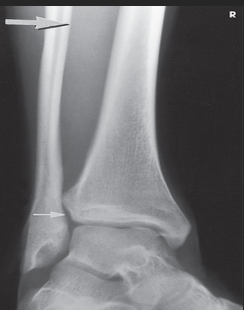

Name this projection.

What type of projection is it?

Which side is the patient turned toward?

Where does the CR enter?

How do you evaluate for a true lateral?

The tibiotalar joint will be well visualized, and the fibula will be over the posterior half of the tibia

How much of the distal tibia and fibula must be included?

Which joint is well visualized?